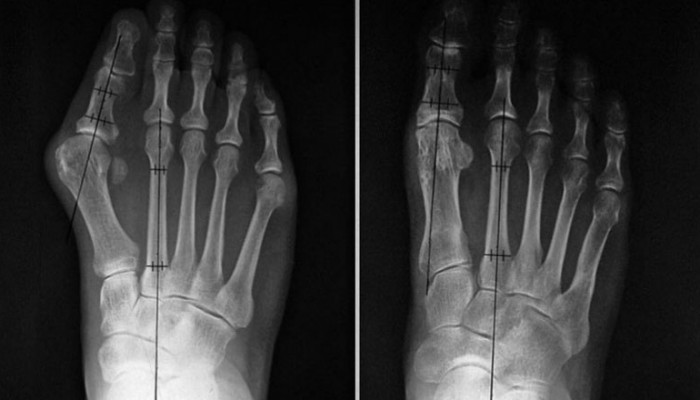

Стадия патологического процесса определяется путем измерения суставного угла между большим пальцем и первой плюсневой костью. В соответствии с этим вальгусная деформация проходит несколько стадий:

- Первая: менее 25 градусов.

- Вторая: 25–35 градусов.

- Третья: более 35 градусов.

На снимках определяется не только деформация костных структур, но и артрозные изменения в плюснефаланговом суставе: сужение суставной щели, неровность ее контура, остеофиты. Обязательна консультация ортопеда-травматолога.